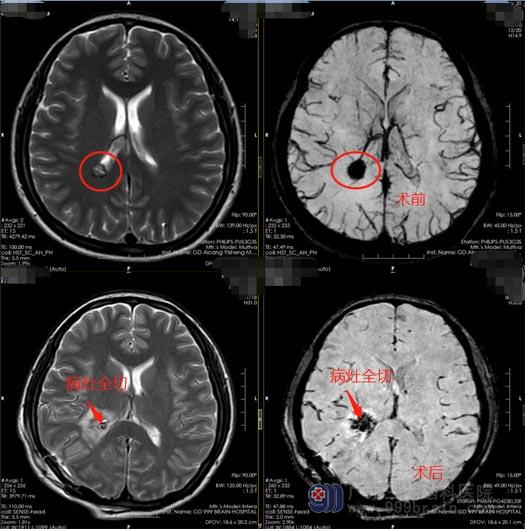

11月25日,蒋姐住在了妈妈同个病房。照顾母亲的同时,她也在完善自己的术前检查,头颅MR检查显示:右侧侧脑室后角占位,考虑海绵状血管瘤可能,需要进行手术治疗。打消了她的顾虑后,12月2日,蒋姐在全麻下行“右侧侧脑室海绵状血管瘤切除术+硬脑膜修补术+颅骨成形术”,利用导航定位血管瘤位置,右侧颞枕部直切口,球囊套筒辅助下切除海绵状血管瘤,术中出血约50ml,未输血。